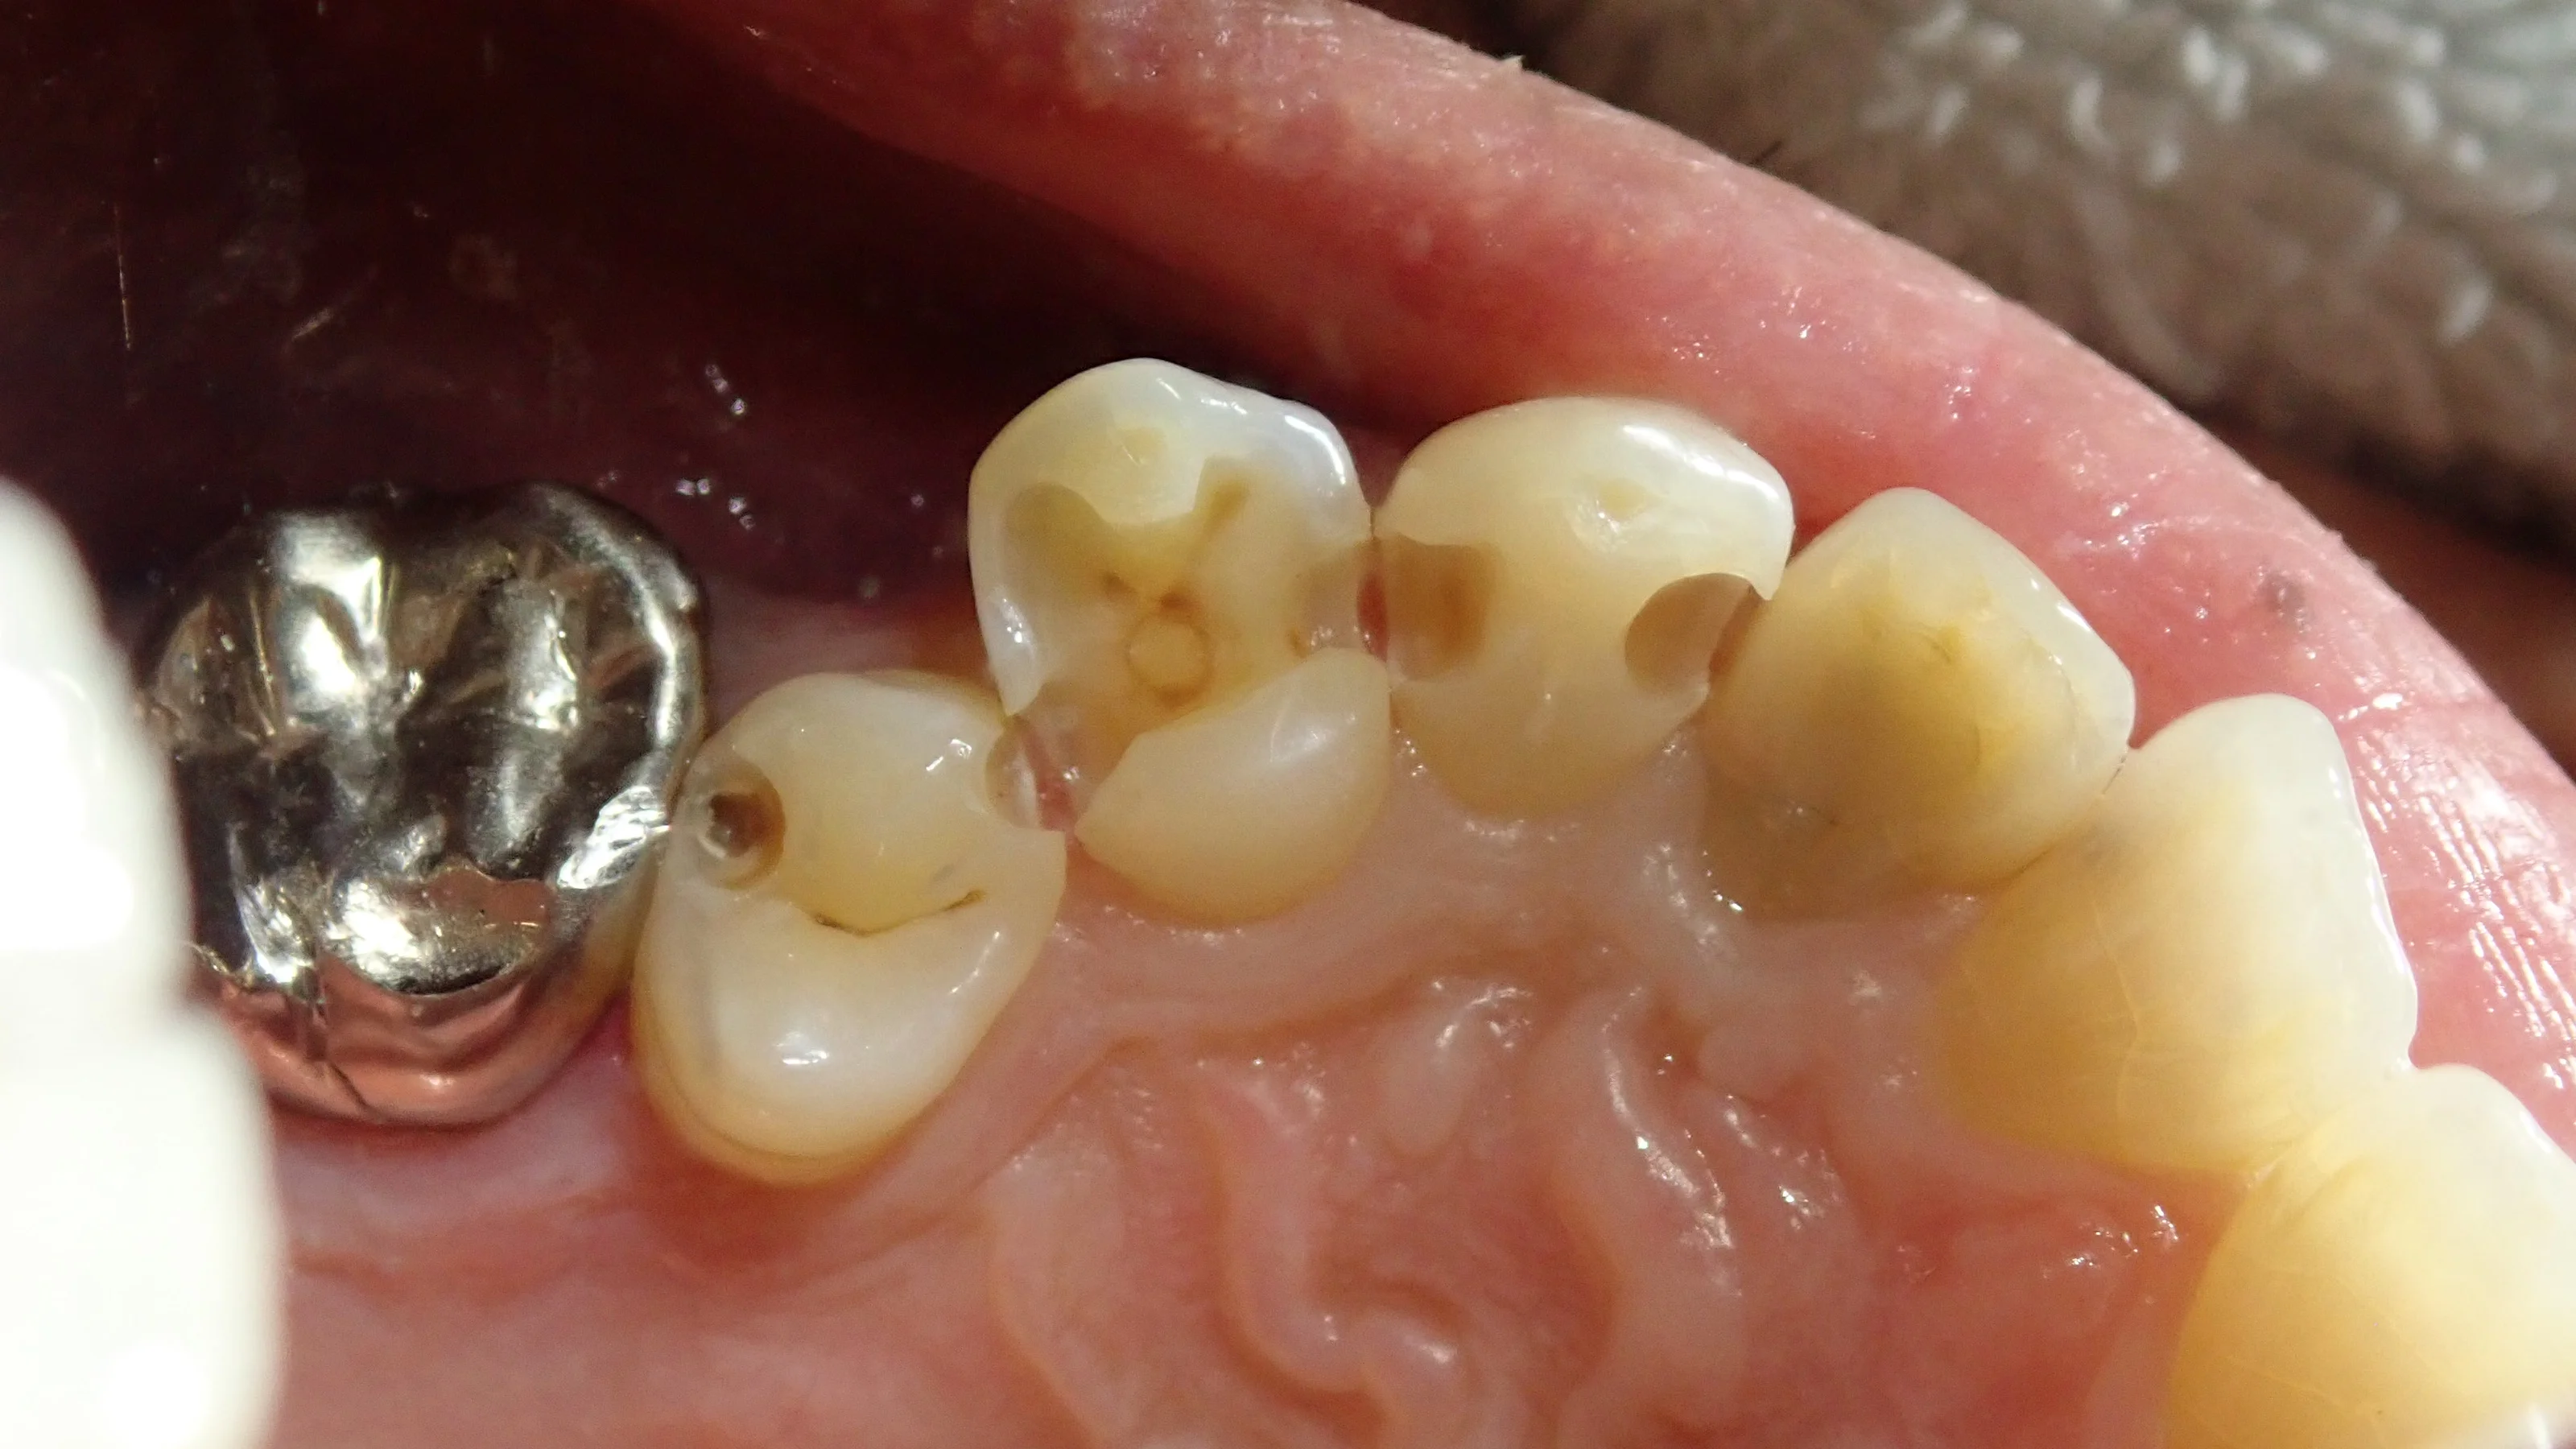

軽く詰め物や歯の表面を削ったのがこちらです。

中が明らかに黒っぽくなっているのが分かるかと思います。